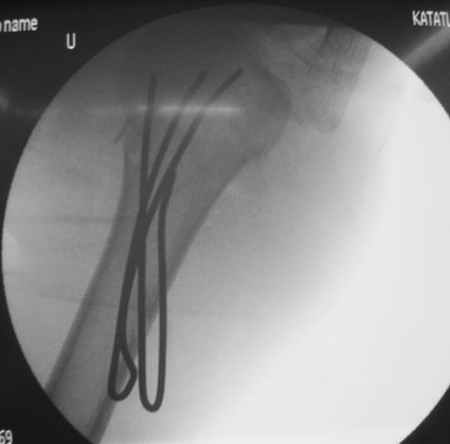

Сегодня взял больного повторно в операционную, не скажу, что повторная репозиция через неделю после первой попытки, была простая.

После удаления спиц попытался манипулировать отломками, но безуспешно, поэтому пришлось пользоваться периостальным элеватором, чтобы устранить смещение отломков и перепровести спицы. Проверил и перепроверил стабильность фиксации под ЭОПом, завтра Рг- будет готов, вот и поглядим....

Посылаю послеоперационные Рг граммы.

Всего Доброго,

Евгений И Чекашкин

Поздравляю, получилось просто замечательно. Если можно, расскажи чуть подробнее, как делали - как вправляли, как вводили спицы, поворачивали ли их?

Спасибо за поздравления:-))

Я и сам доволен результатом. В предпоследнем письме я кратко описал ход операции - закрыто репонировать не удалось( 2 недели с момента травмы и 1 неделя после неудачной репозиции) после удаления пучков спиц, пришлось сделать - 2см разрез на уровне перелома и с помощью периостального элеватора (золотое правило механики) *одеть* головку на дистальный отломок.

Спицы проводил через старые отверстия, вращая пучок импактором- направителем при его введении в головку.